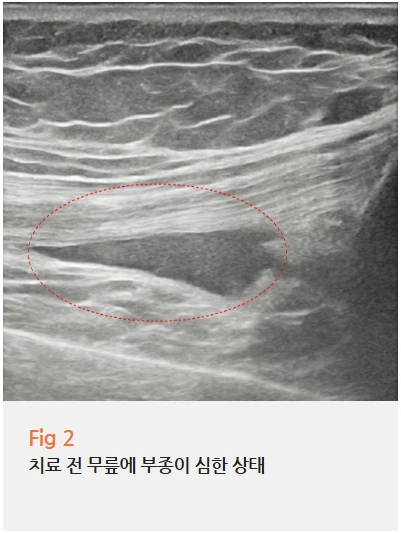

하지만 초음파 검사를 진행하자마자

원인이 명확하게 보였습니다.

무릎에 물이 상당히 많이 차 있었고,

반월상연골파열에 합당한 소견이 확인됐어요.

%EA%B7%B8%EB%A6%BC10.png?type=w966

특히 무릎 뒤쪽 오금 부위에 염증과 부종이 심했는데요.

이 상태에서는 무릎을 굽혔다 폈다 할 때마다

연골과 인대가 자극을 받게 되고,

그 통증이 오금으로 퍼지면서

다리 전체가 당기는 느낌을 받게 되는 거예요.

앉았다 일어날 때 힘이 빠지는 증상도 바로 이 때문이었죠.